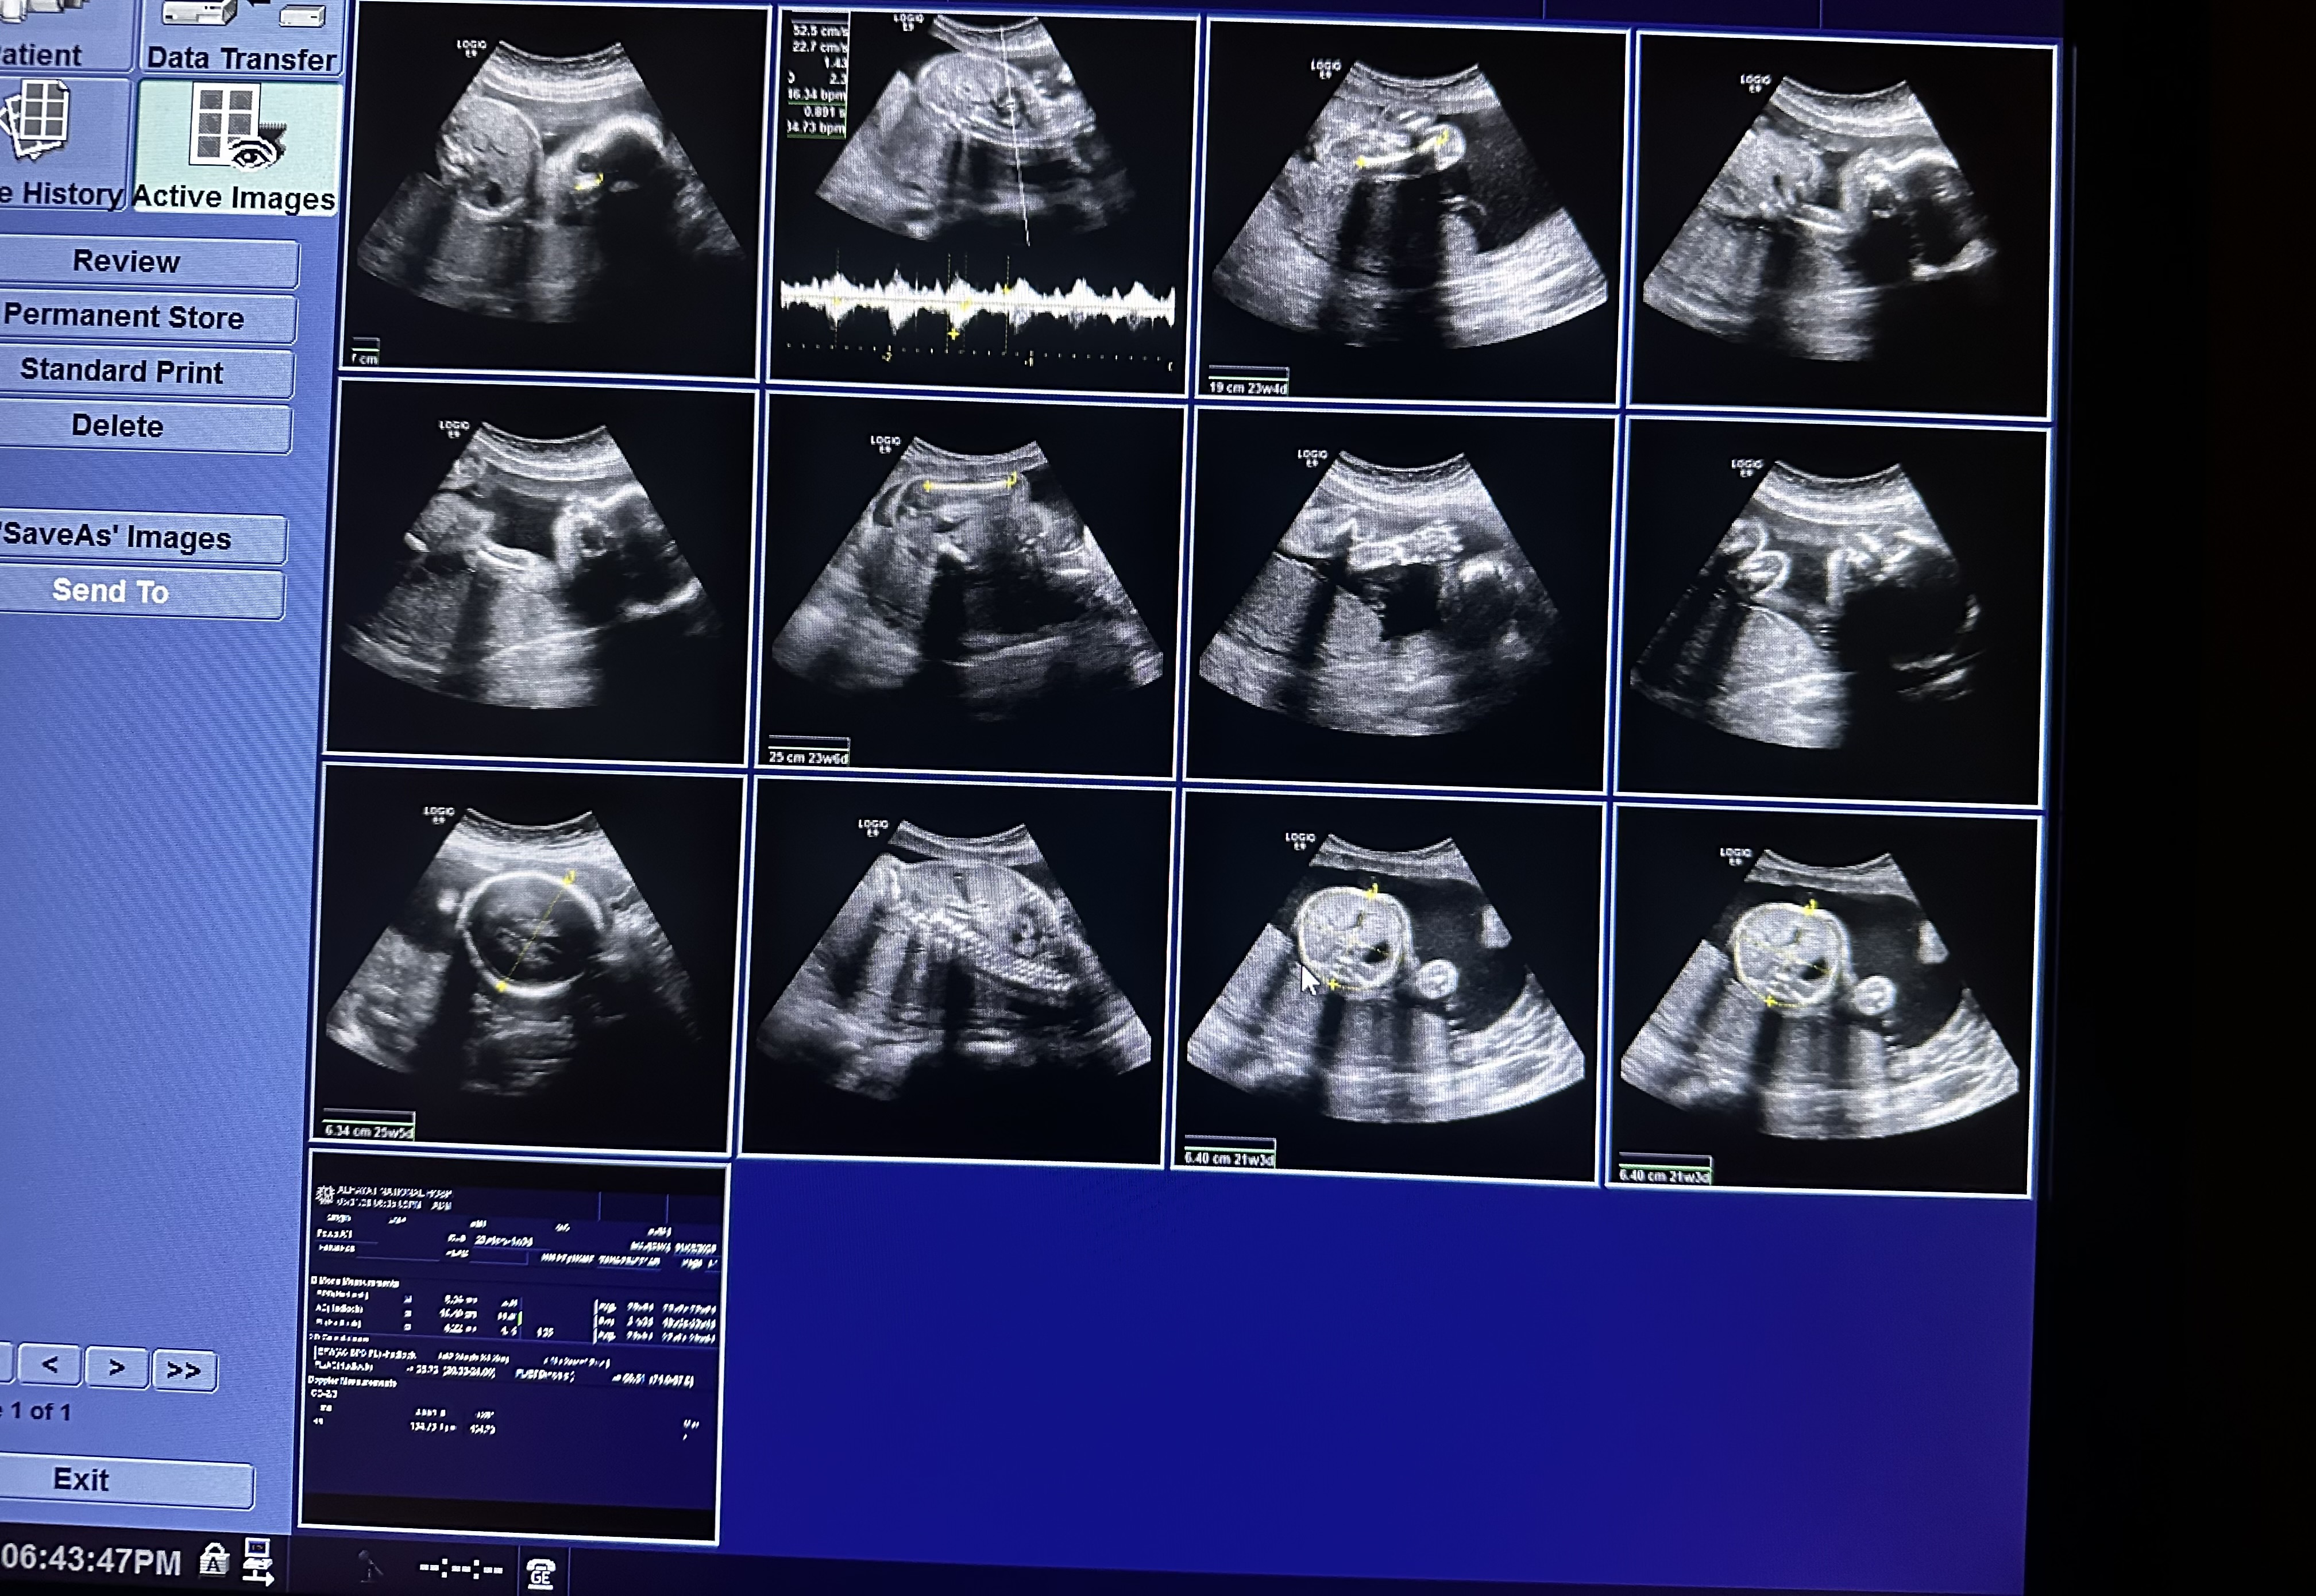

هل يتضح جنس الجنين من هذا المخطط

في الاسبوع ١٧ قالوا صبي في الاسبوع ٢٠ قالوا فتاة وهنا في هذا الصورة الاسبوع ٢٤ مارايكم

غالبا أنثى 0 2026-01-11T09:17:20+00:00

غالبا أنثى